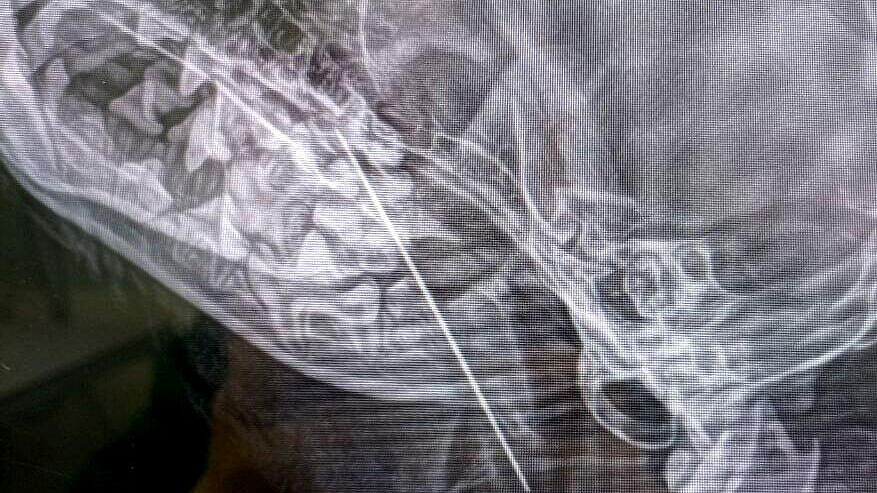

Ветеринары из Москвы извлекли большую швейную иглу из десятимесячной йоркширской терьерши Маруси, которая страдала от непрерывного кашля.

Предварительно считалось, что причиной проблемы была кость от украденной и съеденной форели, однако рентгеновское исследование выявило, что игла застряла в мягких тканях глотки. Спасительная операция была проведена хирургом Натальей Сергеевной Польдяевой, после которой Маруся быстро пришла в себя и вернулась домой здоровой.